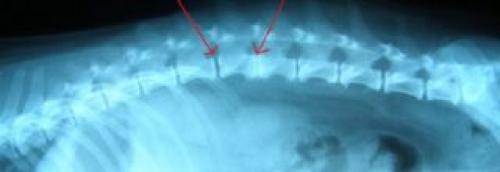

Где в позвоночнике находится хрящ? Из этой структуры состоят такие образования, как межпозвонковые диски. Они представляют собой хрящи в форме эллипса, которые располагаются между двумя соседними позвонками на всем протяжении позвоночного столба.

Межпозвонковые диски выполняют функцию амортизации – они сглаживают амплитуду движений, препятствуют ударам позвонков друг об друга. Каждый диск имеет внутри пульпозное ядро, которое окружено фиброзной капсулой. Патология происходит, когда через дефект в капсуле выходит наружу участок ядра (грыжа диска), который вступает в анатомический конфликт с окружающими образованиями.